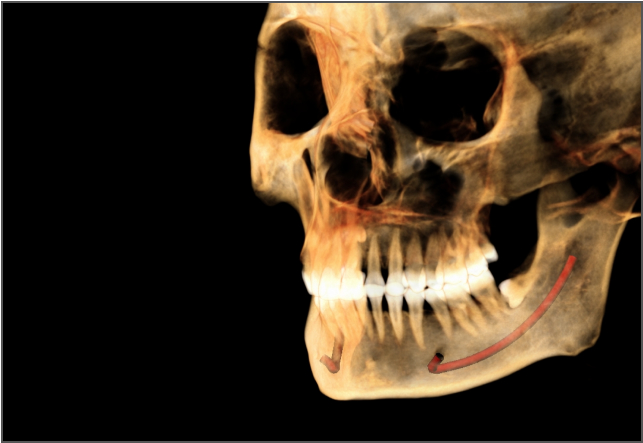

AI 加持,事半功倍 兰台医令的阅片软件包含 AI 神经管绘制、AI 气道分析、AI TMJ分析、AI 牙弓曲线、AI 正畸头影测量等智能图像处理功能,可大大提高诊断效率,实现更好的医患沟通,让医生事半功倍。